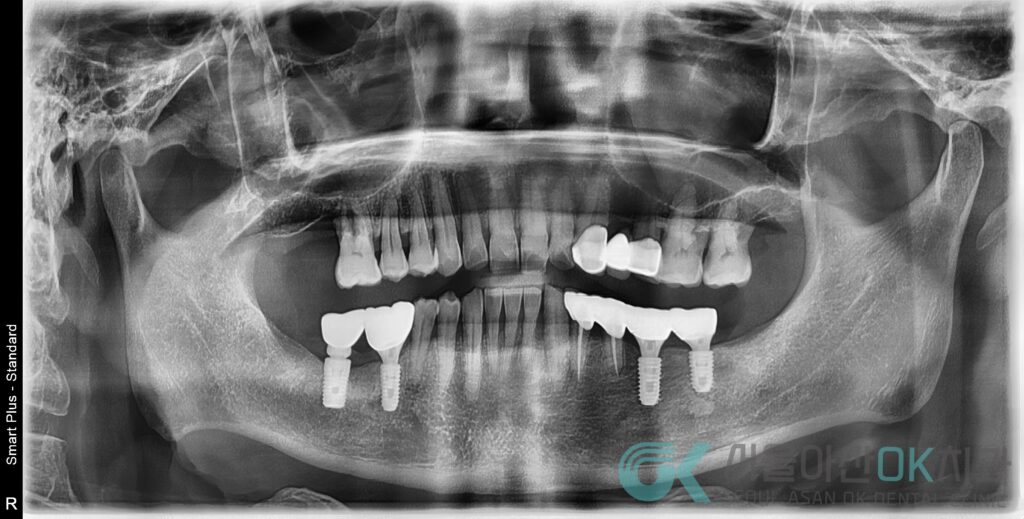

파노라마 촬영과 구내 사진으로 전체를 살펴보았습니다.

그 결과는 조금 달랐습니다.

문제는 특정 치아 하나가 아니라,

전반적인 잇몸 상태였습니다.

치조골이 전반적으로 낮아져 있는

수평적 골 소실이 동반된

만성 복합 치주염 소견이 확인되었습니다.